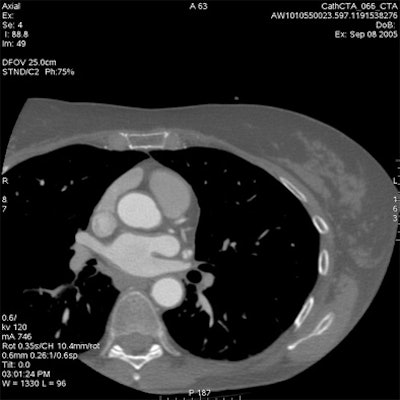

Which image would you rather be responsible for? Small 13-cm FOV (above) provides the best cardiac image quality at the lowest radiation dose compared with medium 25-cm FOV coronary CTA image (below). Thoracic image (bottom) maximizes anatomic coverage but at the cost of additional radiation and potentially more incidental findings. All images courtesy of Dr. Matthew Budoff.

The heart fits in a 25-cm field-of-view, permitting the use of a small bowtie filter in medium-sized and sometimes even larger patients, Budoff said. "We're only worried about the heart," he said.

For example, using protocol parameters of 600 mA, 120 kV, and a heart rate of 60 bpm, a small cardiac bowtie filter (standard 25-cm FOV) permits cardiac images to be acquired at dose-length product (DLP) of 474 (8.0 mSv), Budoff said. A medium bowtie filter (allowing reconstruction to 36-cm FOV) affords a dose of 791.4 DLP (13.4 mSv).